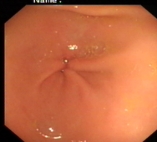

内镜下表现:黏膜红白相间,以白色为主,黏膜皱襞变平或消失,部分黏膜血管显露,可伴有黏膜颗粒或结节状等表现。如伴有肠化生于电子染色窄带成像放大内镜(NBI ME)下发现胃粘膜上皮细胞表面的脑回样结构嵴部的纤细浅蓝色线样结构。病理活检可进一步确诊。

正常胃表现